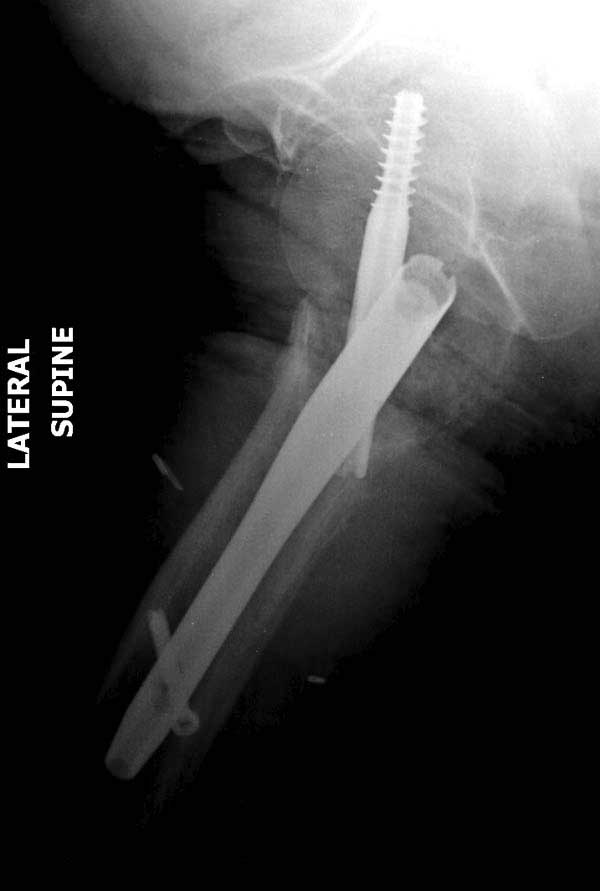

Первые снимки показывают технические погрешности установки DHS. Не была достигнута репозиция, конечность в флексии и шейка в ротации. Сегодня все меньше обращают внимание на параметры для оценки репозиции (S контуры Lowell в обеих проекциях и Garden Alignment Index, в норме 155 и 180 градусов), хотя такие простые тесты помогли бы дорепонировать смещение. Винт находится сзади в головке, что при нагрузке поменяет вектор и вместо компрессии в линии перелома срежет головку-Cut Out!

В зависимости от дистанции линии перелома и латерального кортекса надо использовать разной длины barrel, т.е. конец баррели не должен доходить до пределов перелома. Здесь конец длинного ствола упирается в медиальный фрагмент, что мешает созданию компрессии, а более короткий barrel создал бы запас для компрессии. В боковой пластине вместо 4х можно было ограничится двумя шурупами, потому что головка шурупа в 4.5 мм выдерживает давление до 350 кг.